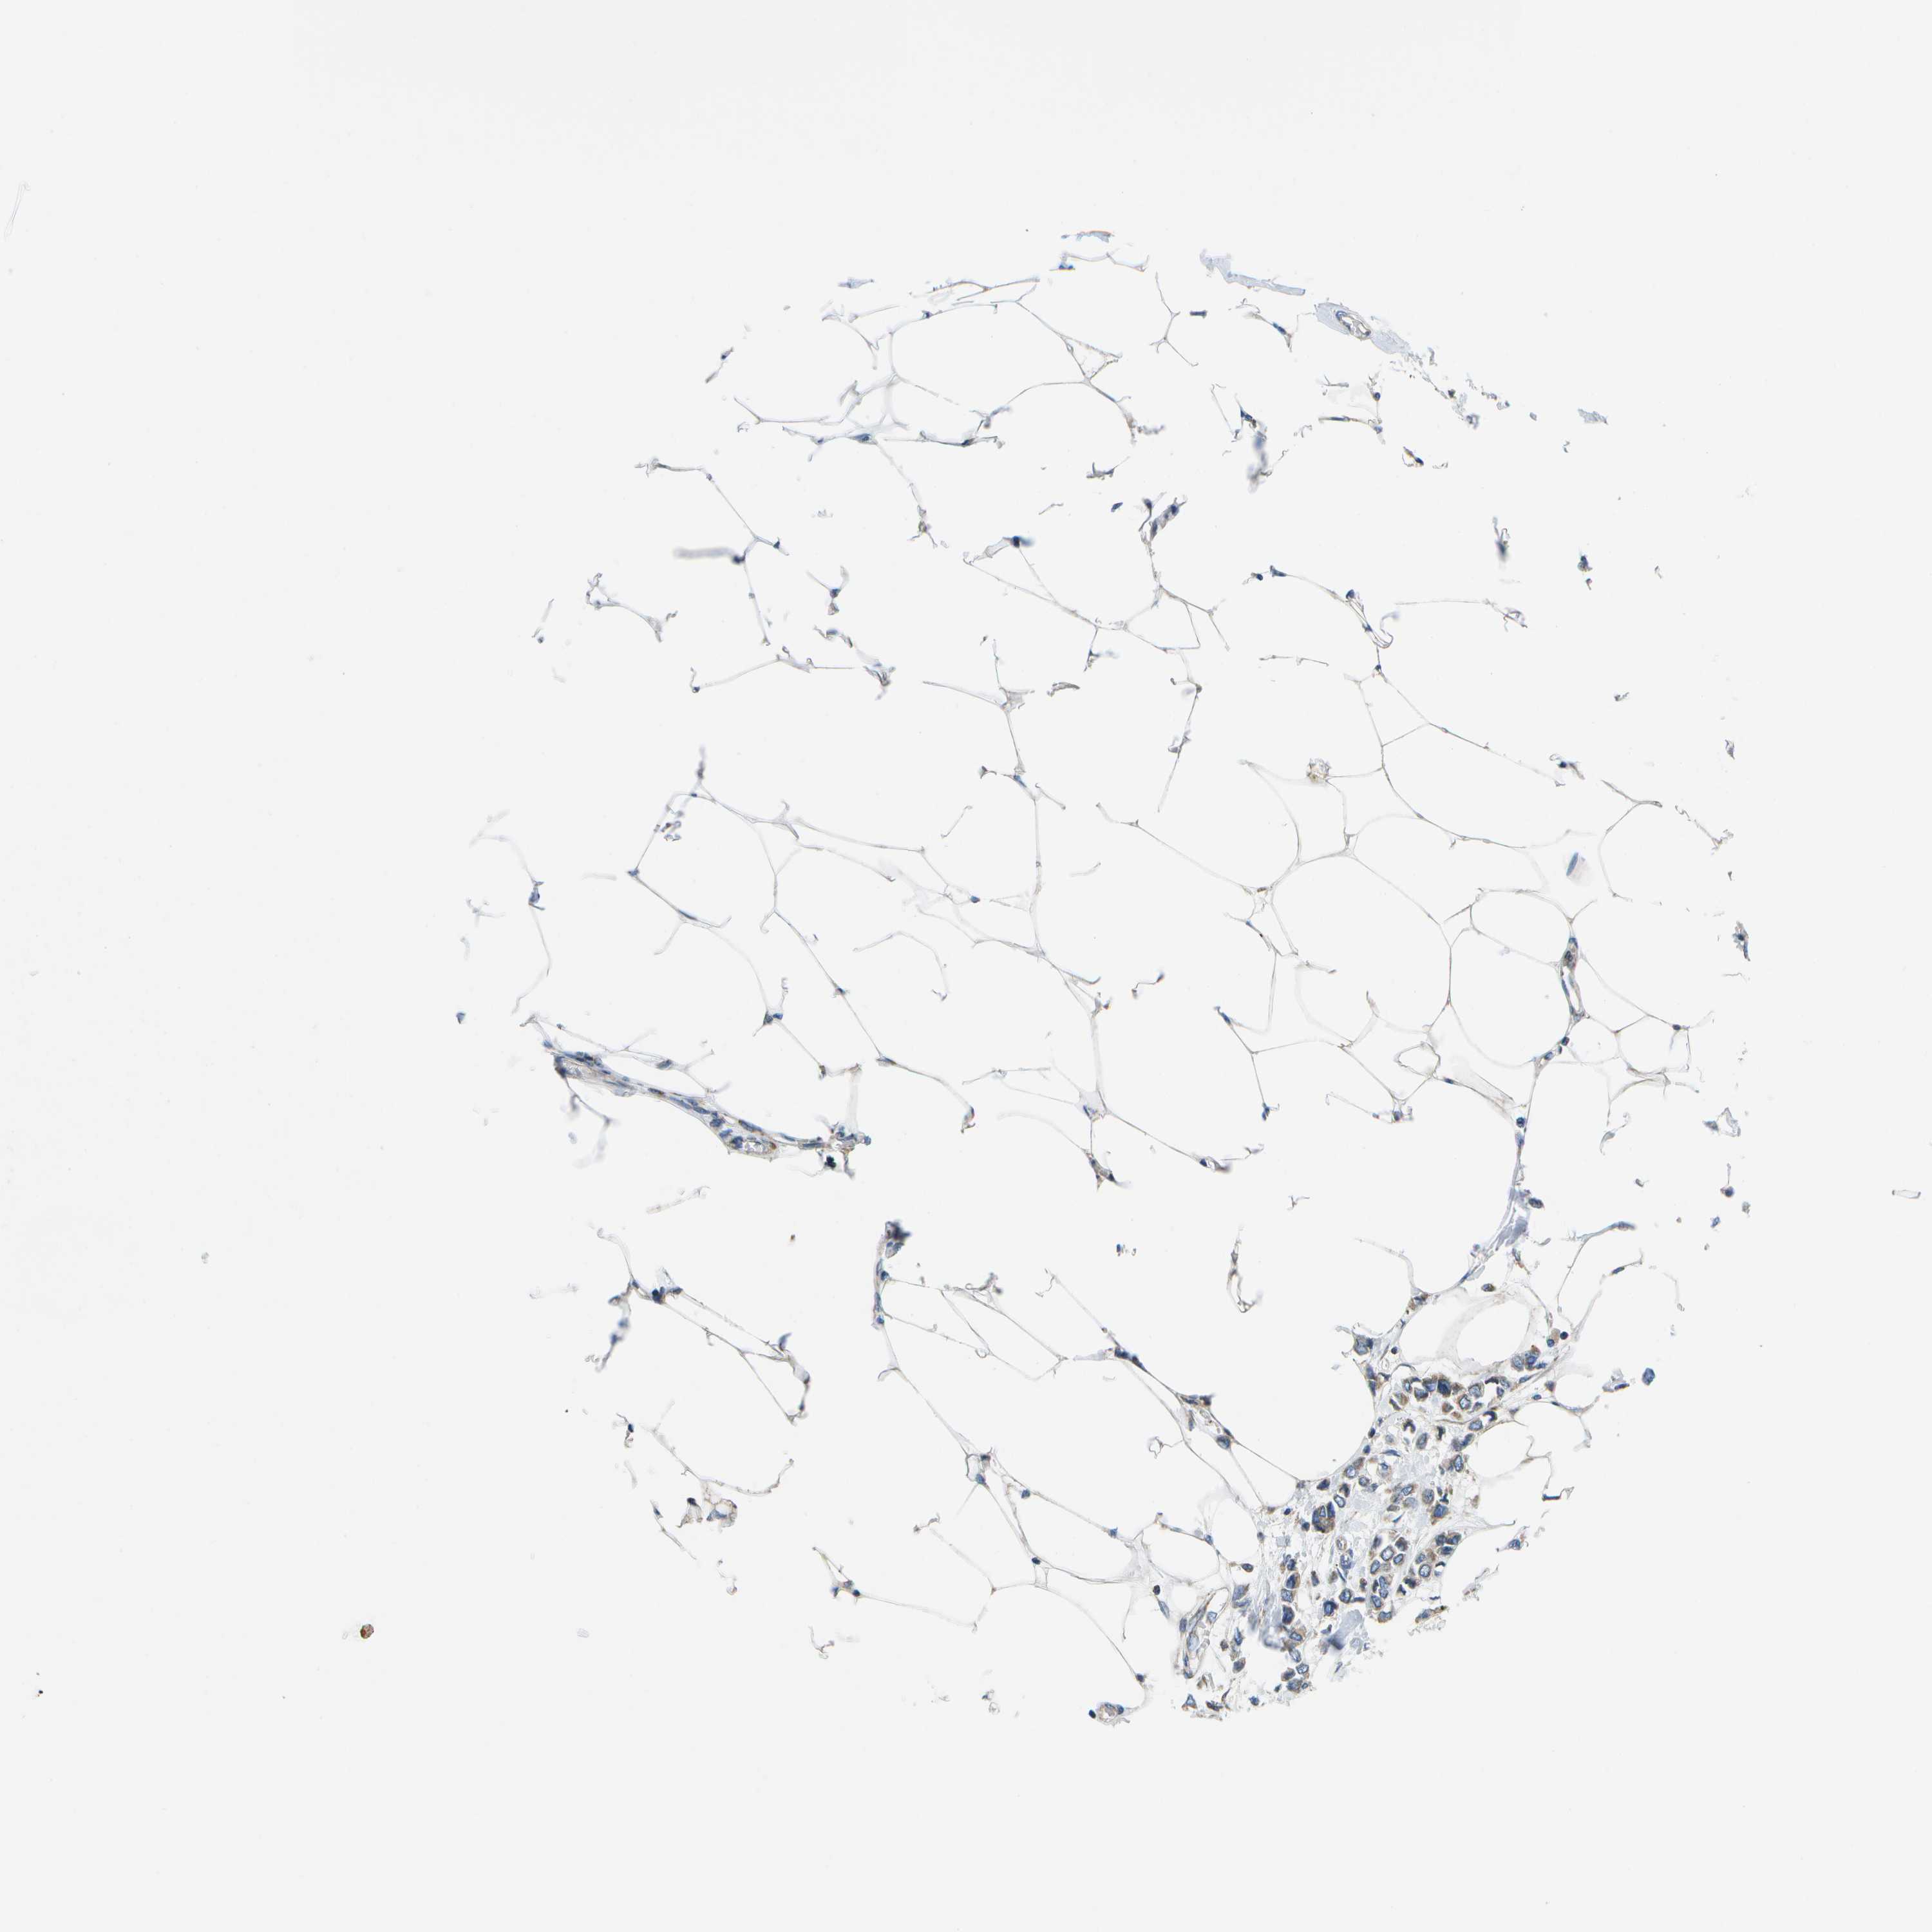

Average pTPM 0.9

Number of samples 1022